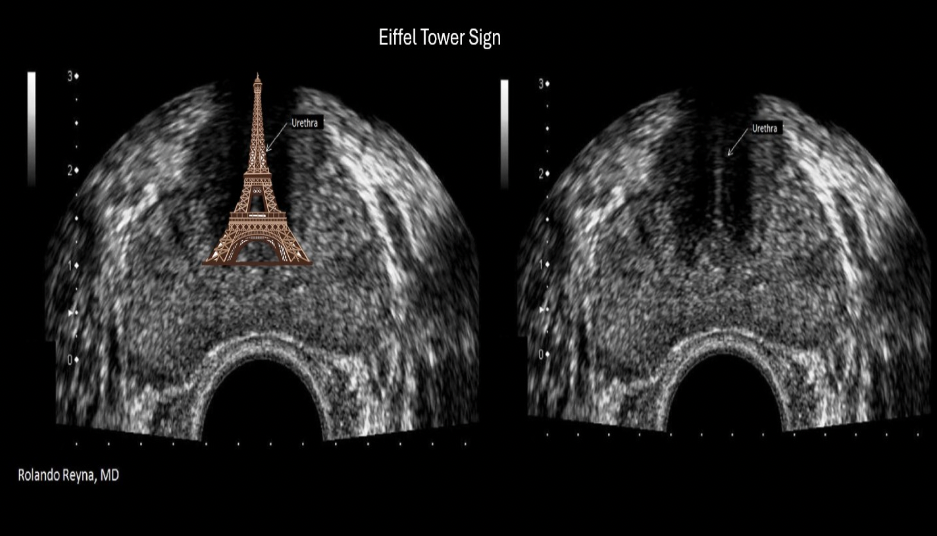

The Eiffel tower sign on ultrasound refers to:

C. normal prostate

Eiffel tower sign refers to shadowing created by dense tissues in the area of the urethra and verumontanum of the prostate.